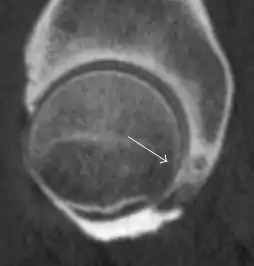

Synovial chondromatosis can be confidently diagnosed by X-ray when calcified cartilaginous chondromas are seen. However, other synovial proliferative processes, such as pigmented villonodular synovitis, require MRI for accurate diagnosis, although noncalcified synovitis can be suspected in radiographs by indirect signs, such as soft tissue swelling and/or erosions in the femoral head, femoral neck, or acetabulum (Figure 7).[1]

Figure 7:

Axial CT image of pigmented villonodular synovitis eroding the posterior cortex of the femoral neck.[1]

Sagittal T2* gradient echo image showing a posterior soft tissue mass with hypointense areas secondary to hemosiderin deposition.[1]